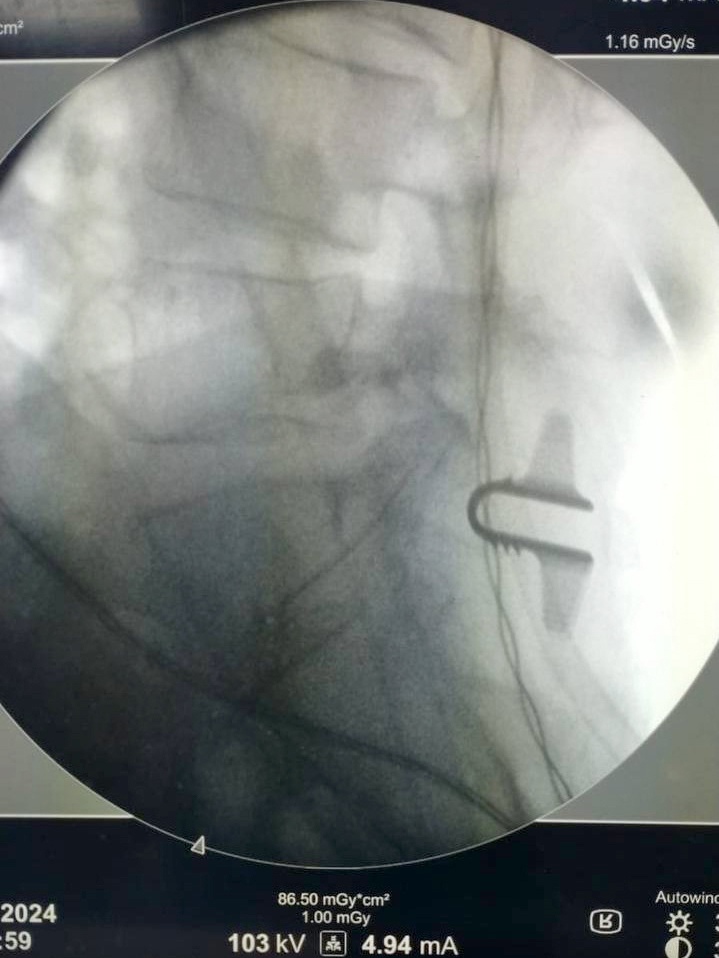

В Кирове гостье из соседнего региона выполнили малоинвазивную хирургическую операцию по удалению грыжи межпозвоночного диска с динамической стабилизацией.

– При таких операциях выполняется небольшой разрез, для малоинвазивного доступа устанавливается специальный расширитель. Под микроскопическим контролем мы расширяем межпозвонковый промежуток, высвобождаем сдавленный нервный корешок и удаляем грыжу межпозвонкового диска. Для снижения дальнейшей нагрузки на диск между дугами позвонков устанавливается титановый имплант, – поделился врач-нейрохирург Сергей Кошкин. – На фоне проведенного лечения у пациентки значимо снизилась интенсивность болей, увеличилась переносимость бытовых нагрузок.